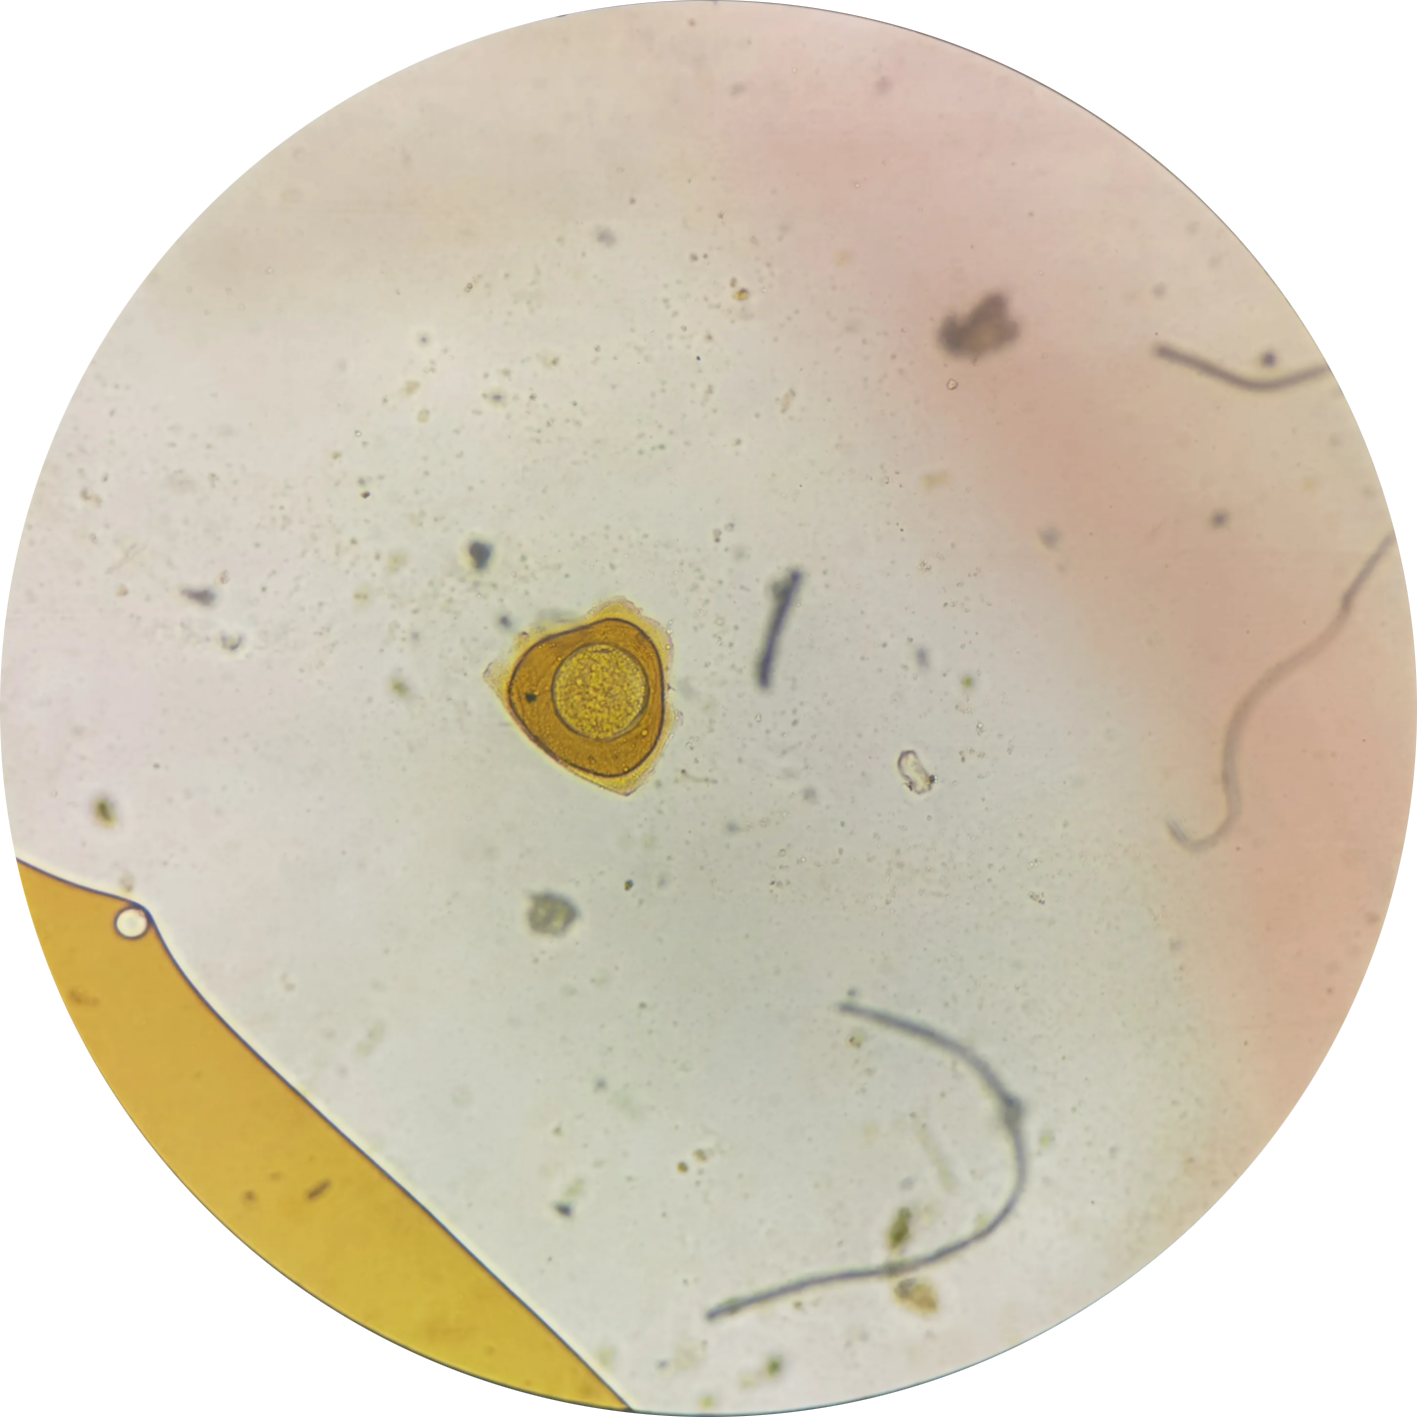

姜片虫囊蚴